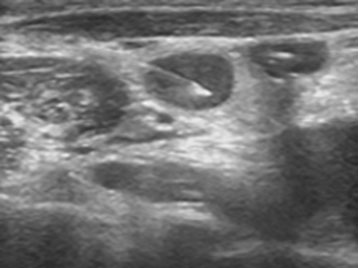

Ultrasound guided FNAC (procedure)